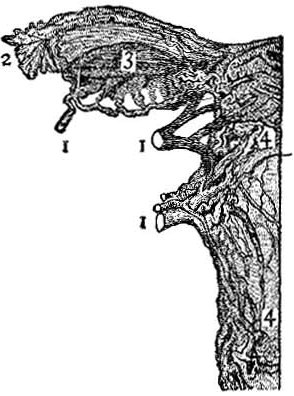

Blood-Vessels Surrounding Uterus.—The uterus is well supplied with blood-vessels, as Fig. 6 shows. Indeed, there is all over the walls of the uterus and through its tissue a vast network of these vessels. Whenever, for any reason, the circulation of the blood through the pelvis is disturbed, these blood-vessels are likely to become engorged, over-filled, producing congestion and inflammation.

All Parts Closely Related.—The close relation of these blood-vessels to the blood-supply of the bowels, liver, etc., makes it possible for most serious disturbances to take place even from slight causes.

Study the Illustrations.—By studying these illustrations it can be readily seen how an over-distended rectum may produce such an impediment to the circulation that there will be congestion of all the neighboring parts. Or, the intestines themselves may become over-distended with fæcal matter, or gas, from dyspepsia, and the pressure induced thereby may be sufficient to interfere with the free circulation of these parts, and thus uterine congestion produced.

It is also seen how improper dress may compress the organs about these parts, and thus inter[Pg 11]fere with the circulation. Again, it is easily understood, simply from studying the illustrations alone, how any of these causes might produce dislocation of the uterus itself.

| Fig. 8. This figure illustrates the course followed by an ovum. The ripened egg leaves the ovary (1), passes down the Fallopian tube (2), and thence into the uterine cavity (3). | Fig. 9. An exceedingly minute piece of an ovary, highly magnified. It shows eight ova or eggs. |